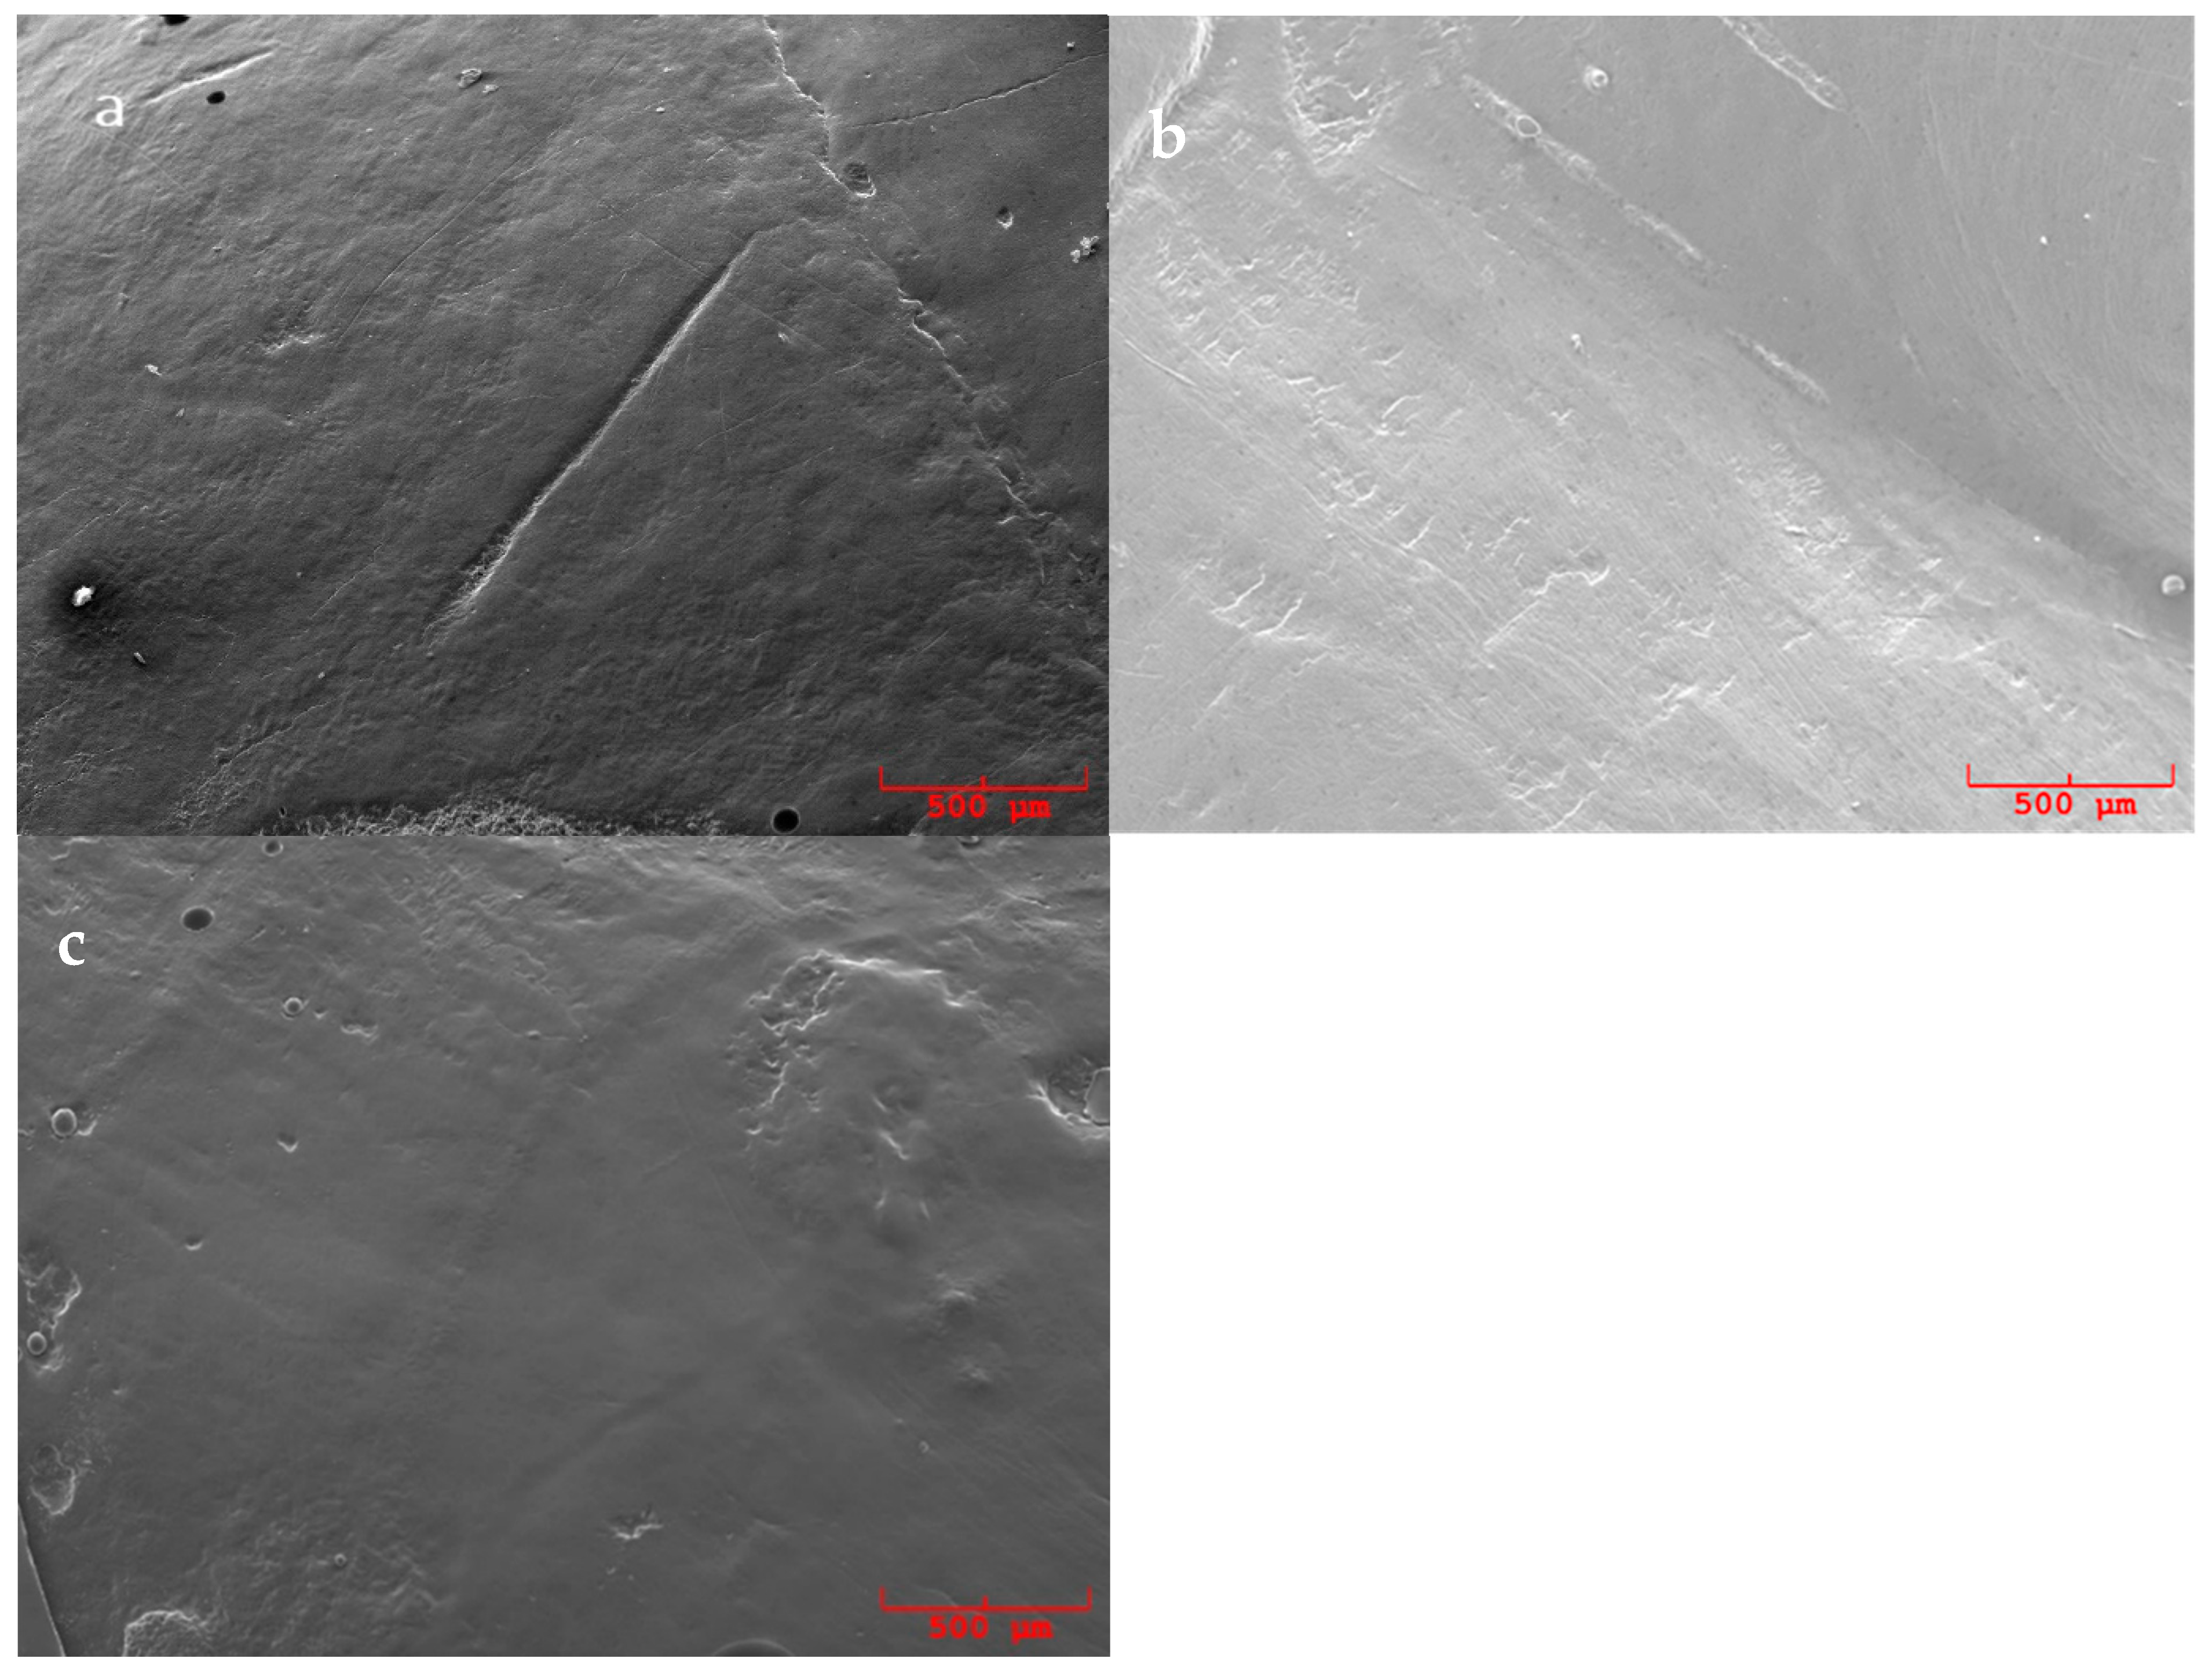

3.2. SEM Evaluation

- Smoother surface;

- Unchanged surface;

- Rougher surface.